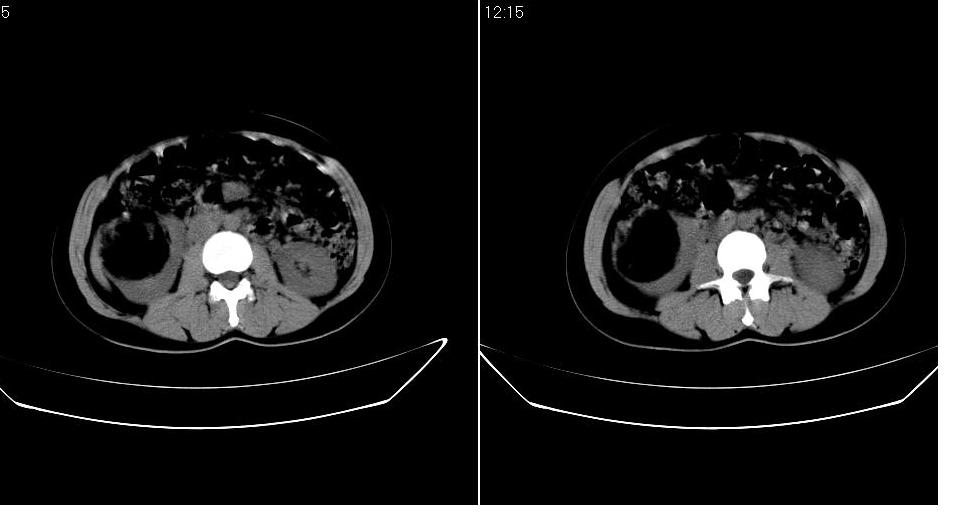

以下是引用求知若渴在2007-9-10 20:08:00的发言:[br]病变以脂肪成分为主,应该是错构瘤。另肝内胆管结石

以下是引用xulianj在2007-9-10 20:51:00的发言:[br]错构瘤,支持。含脂肪成分较多,证明较为成熟。

以下是引用王仕学在2007-9-10 21:34:00的发言:[br]有脂肪密度,哪怕是一点点,首先考虑错构瘤。还是增强吧,好说些!